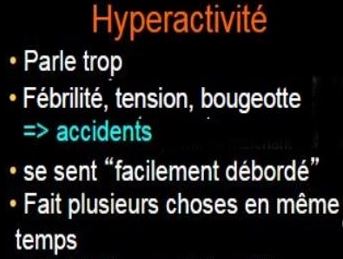

H Y P E R A C T I V I T E |

• Toujours en mouvement • Court et saute sans raisons • Tendance à faire pipi au lit • Ne sais pas s’occuper calmement |

• Se sent souvent agité et à cran • Parait occupé mais fait peu de choses • Ne sait pas s’occuper calmement • Comme conduit par un moteur |

• Nerveux • A la bougeotte avec ses membres • A du mal à rester assis longtemps • Peut parler excessivement • Jobs les plus actifs ou extraordinaires |

2 Hyperactivité  Agrandir cette liste  Ecouter le texte ci-contre Hyperactivité cérébrale aussi …  |

► A l’âge